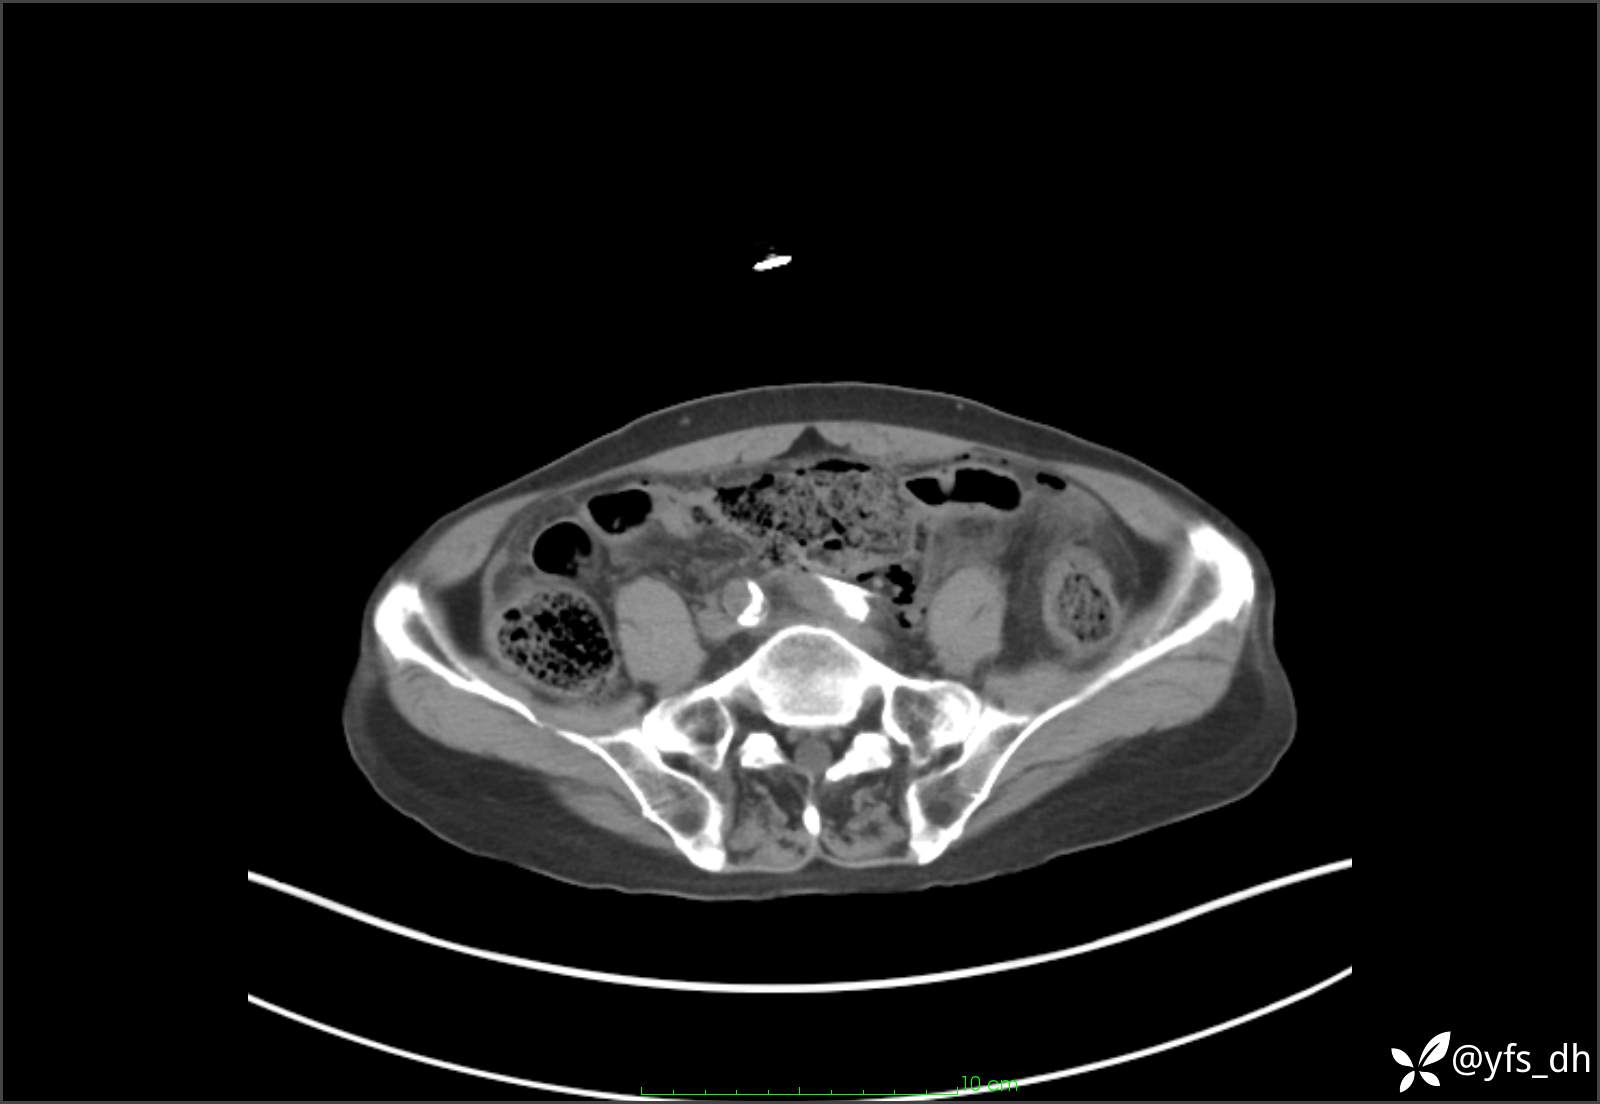

1.简要病史:患者4天前突发上腹部疼痛不适,但可以忍受。3小时前饭后突然加重,不能忍受后就诊。

2.简要手术记录:术中见腹盆腔大量肠液及粪便,乙状结肠中下段见一约3cm的破口。